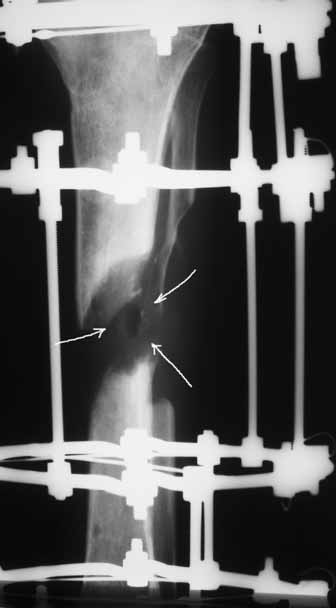

С места аварии в районную больницу, где произвели ампутацию правой голени. Дальше в клинику спец. помощи, где на левой голени были удалены нежизнеспосбные инфицированные отломки, (дефект 13 см) и наложен аппарат Гофмана. Детали неизвестны. Со слов больного, инфекционный процесс левой голени купирован не был. В феврале аппарат был снят и произведен остеосинтез гвоздем (before1;2). В мае, объективно: В нижней трети голени функционирует свищ, отделяемое гнойное: золотистый стафилокок, чувствительный к большинству антибиотиков.

1 июня произведено удаление гвоздя, дренаж костномозгового канала, остеосинтез аппаратом Илизарова ( after 1; 2).